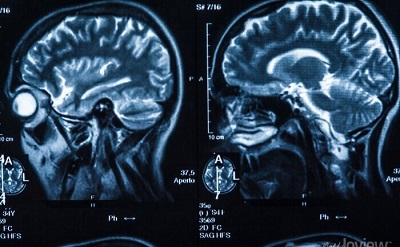

Foto: Ilustração